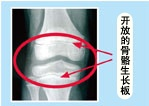

IGF-1主要由人肝细胞合成和分泌,对机体生长发育起重要调节作用。是一类促进细胞生长、具有胰岛素样代谢效应的因子。IGF-1受营养状态、激素、遗传等多因素调节,在心血管疾病、内分泌代谢病及肿瘤等的病理生理过程中发挥重要作用 国内外药监局:GH治疗矮小症 n 1985 儿童生长激素缺乏症(GHD) n 1993 慢性肾功能不全肾移植前 n 1996 HIV感染相关性衰竭综合征 n 1996 先天性卵巢发育不全(Turner综合征) n 1997 成人GHD n 2001 小于胎龄儿(SGA) n 2002 Prader-Willi综合征 • 2003 特发性矮身材(ISS)是一类原因不明,病因 十分复杂的矮小症(包括家族性矮小) 开始治疗年龄与疗程: ® 开始治疗年龄愈小,效果愈好 ® 生长激素缺乏症:发现马上用 ® 其他:2-3岁起 ® 青春期及其后期,效果较差 ® 疗效:青春期前3个月2-3cm左右 1年8-12cm ® 疗程:至少1~2年(矮身材诊治指南) 生长激素治疗安全性? l 国家验证(药监):无毒、安全、有效 l 医院保障:管理 l 医生作用:把关 l 常见副作用: l 局部皮肤红肿、暂时甲状腺素水平↓ l 水肿、头痛、关节痛 l 禁用:肿瘤、白血病、骨骺已闭合、高血糖 家长最常见的误区 误区一: 认为父母高,孩子一定高。 虽然身高和遗传关系紧密, 后天发挥同样重要。 误区二: 男孩没变声,女孩没来月经,还不算发育,不着急。 变声和月经是标志孩子进入青春期发育后期的标志,即骨骼生长区(骨骺)已经接近闭合,身高开始进入停长倒计时。 误区三: 我的孩子是晚长 晚长:骨龄落后于年龄2岁以上,且生长激素激发试验正常. 骨龄正常(与孩子年龄相当):排除晚长可能。如果目前身高已矮小,那么肯定赶不上同龄孩子身高。 误区四: 孩子不喜欢吃饭,挑食,不爱运动才会导致身材矮小,只要补充营养,孩子身高肯定能够正常 3岁以后调控孩子生长的关键因素不再是营养,而是生长激素。 误区五:只要骨骺没闭合都可治疗,等长大些了再治疗也不迟 1. 但年龄越大,骨龄也越大,生长时间缩短;骨龄越大对药物的敏感性越差,疗效就越差; 2. 年龄增长,体重随之增加,药物剂量增加,费用也越多。 治疗年龄越小,效果越好,花费越少 误区六:听说吃增高药效果好,不用打针 生长激素不能吃,会被消化液破坏。口服增高药或是维生素蛋白质类营养素,或含有导致骨骺提前闭合的作用成分,吃了药是长个了,但自身生长潜力却被消耗,导致最终成人身高矮小。 (责任编辑:Doctor001) |